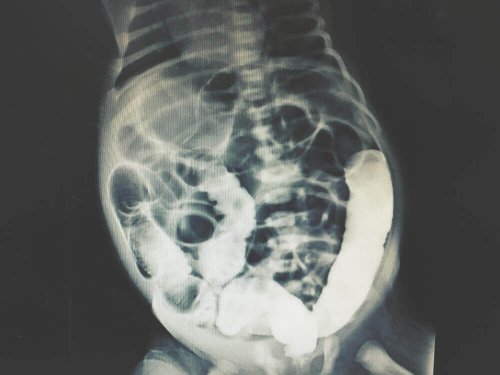

“X-ray peritoneal dialysis”.